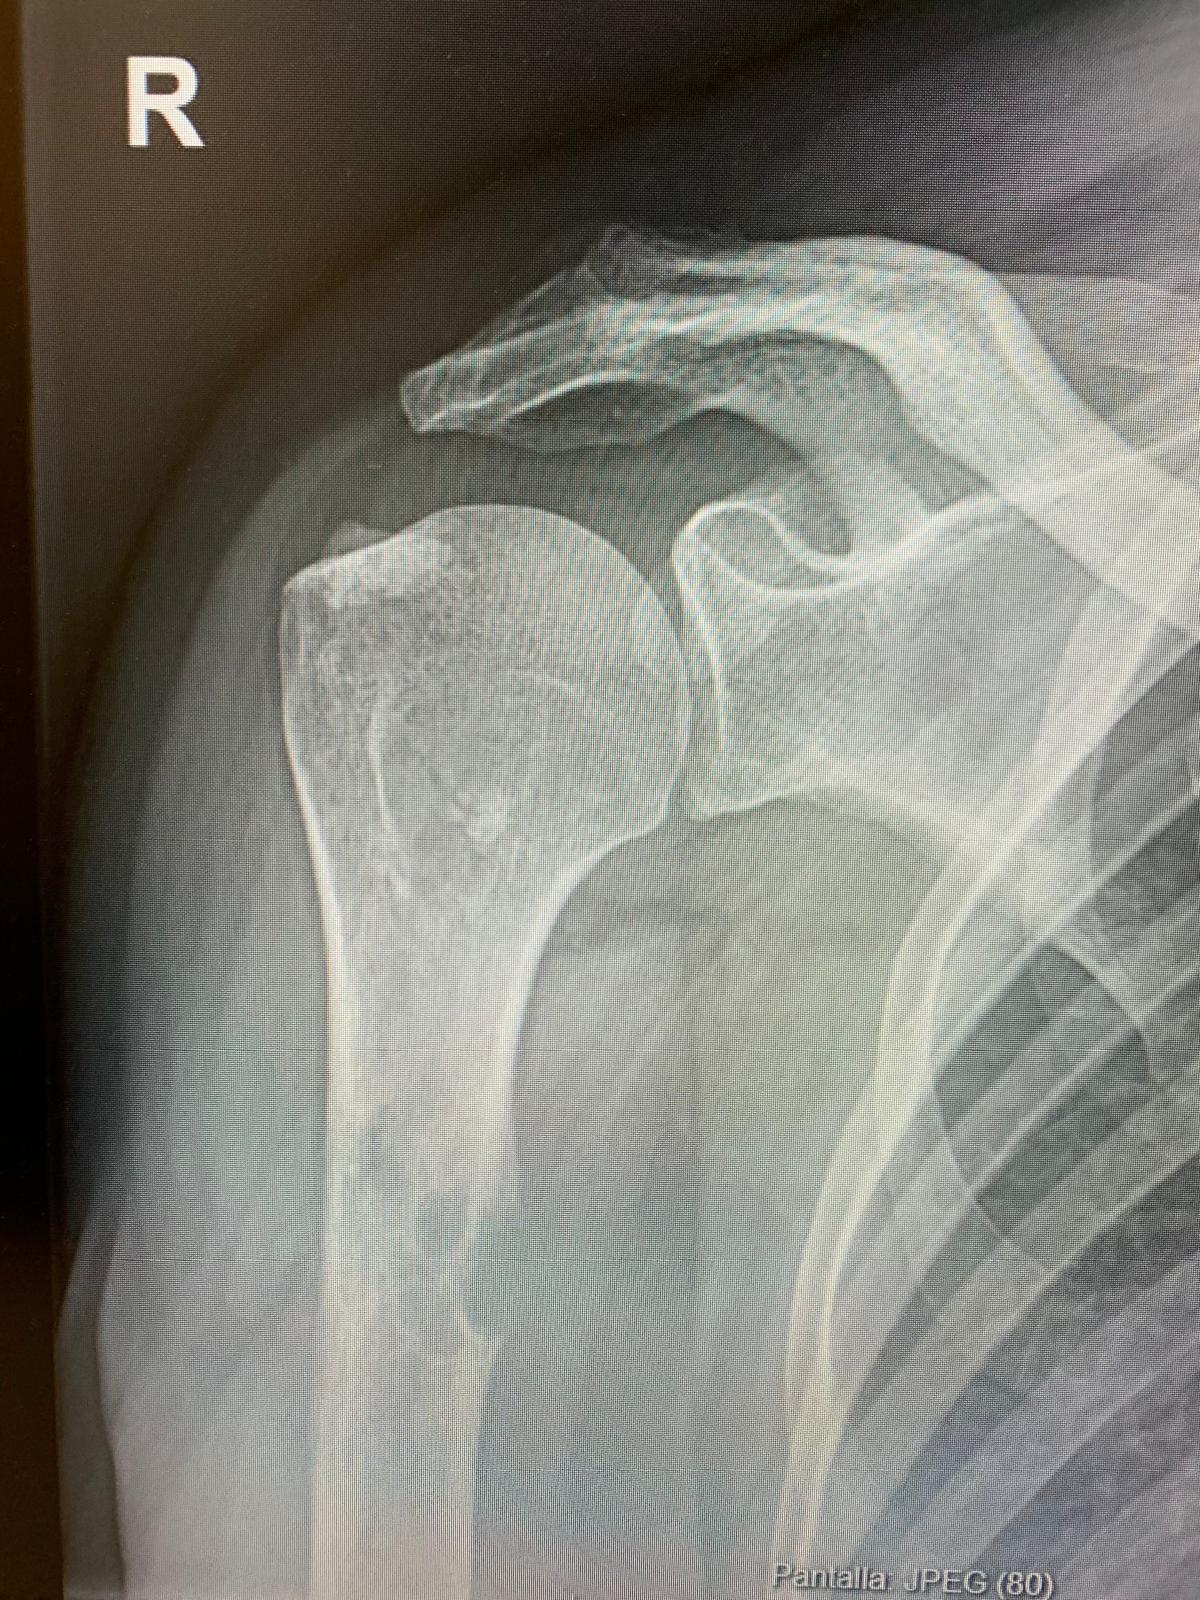

En su primera consulta de Atención Primaria se pauta analgesia sin otra prueba complementaria. En la consulta de seguimiento, dada la ausencia de mejora del dolor, se solicita radiografía de hombro de carácter normal. Se realiza la radiografía el 14/08/2024. La paciente decide acudir a Urgencias el 13/09/2024 ante la persistencia de la clínica. No refiere nueva clínica sistémica.

En la consulta de urgencias se revisa radiografía realizada y se objetiva lesión lítica a nivel de húmero. Dadas las características radiológicas y el antecedente oncológico se debe sospechar de malignidad como primera posibilidad diagnóstica.

La paciente ingresa en Hospitalización Parcial y se confirma la presencia de múltiples metástasis óseas (húmero derecho, rama isquiopubiana izquierda, acetábulo y cabeza femoral izquierda). Se inicia tratamiento con bifosfonatos a la espera del resultado de Anatomía Patológica de la biopsia humeral realizada el 02/10/2024.